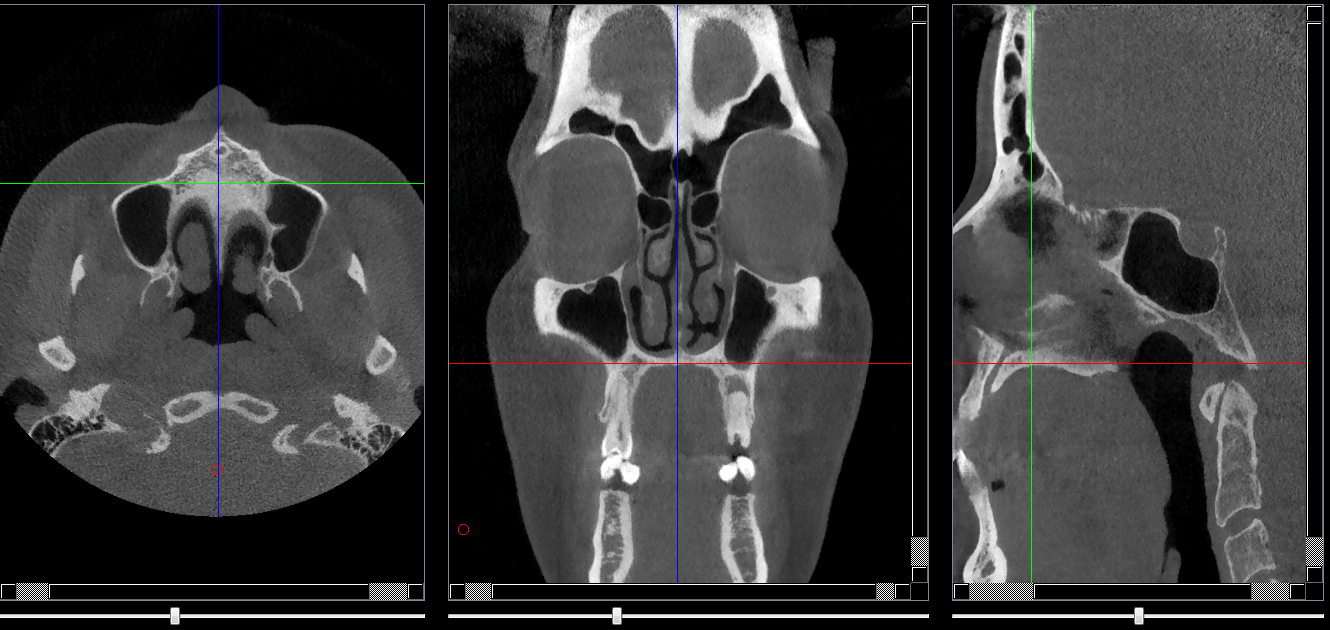

Structures osseuses

Palais dur

Repères anatomiques

- Coupe transversale

- Début : Procès alvéolaire sup

- Fin : cornet nasal inf

- Coupe frontale

- Début : Procès alvéolaire ant

- Fin : Oro-pharynx

- Coupe saggitale

- Début : Procès alvéolaires du secteur droit

- Fin : Procès aléolaire du secteur gauche